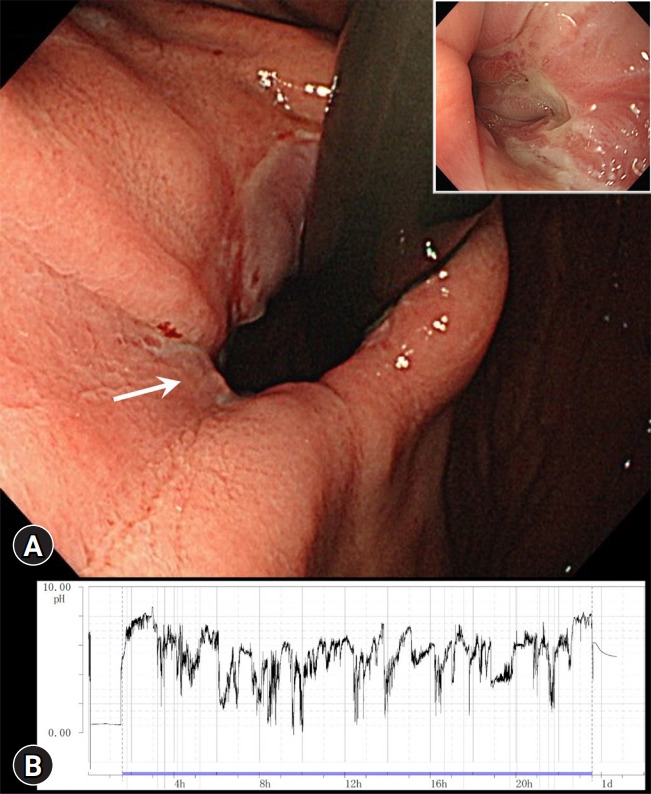

Antireflux mucosectomy for refractory gastroesophageal reflux disease following peroral endoscopic myotomy.

经口内窥镜肌切开术后顽固性胃食管反流病的抗反流粘膜切除术。